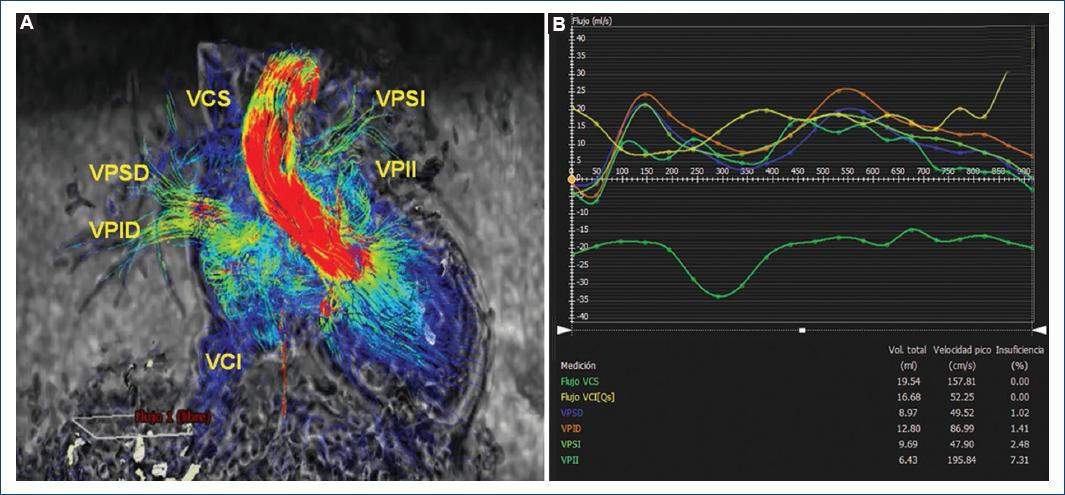

En este caso se realizó una reconstrucción en secuencia de flujo 4D coronal fusionada de la conexión cavopulmonar total y en secuencia de flujo 4D en respiración libre (Fig. 3), cubriendo el área de interés entre el túnel de Fontan (por encima de la entrada de las venas hepáticas), la vena cava superior (por debajo de la vena braquiocefálica) y las arterias pulmonares derecha e izquierda hasta los niveles de las ramas segmentarias, permitiéndonos evaluar la permeabilidad del tubo de Fontan y calcular el Qp/Qs (Fig. 4), donde se determinó la permeabilidad del mismo y la ausencia de circulación colateral aortopulmonar.

Figura 4 A: resonancia magnética cardiaca en secuencia de flujo 4D con líneas de corriente. B: tabla de cuantificación Qp/Qs para valorar la presencia de colaterales. VCI: vena cava inferior; VCS: vena cava superior; VPID: vena pulmonar inferior derecha; VPII: vena pulmonar inferior izquierda; VPSD: vena pulmonar superior derecha; VPSI: vena pulmonar superior izquierda.